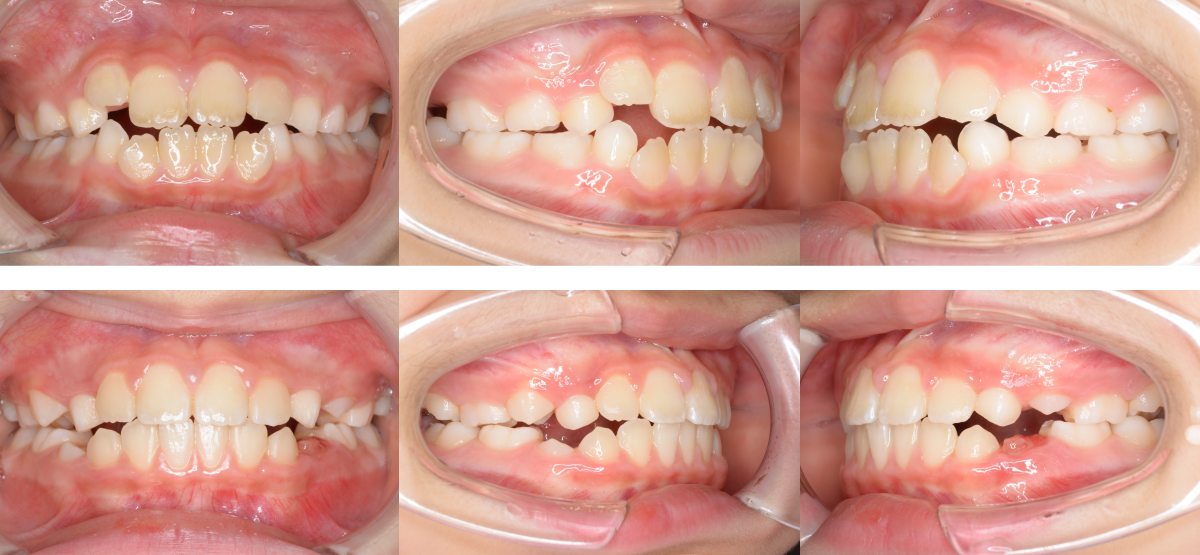

②子供(小児)の開咬の矯正治療例(8歳女児・治療期間1年6か月)

| 年齢・性別 | 8歳女児 |

| 治療期間 | 1年6か月 |

| 抜歯 | なし |

| 治療費 | 37万円(調整費、保定費まで含む総額制) |

| 備考 | インビザラインファースト |

| リスク・副作用 | 痛み・治療後の後戻り・歯根吸収・歯髄壊死・歯肉退縮 |

前歯の萌出スペース不足を主訴に来院されました。

治療法は第一期治療(小児矯正)で、治療期間は1年5か月です。

可撤式矯正装置を用い、萌出スペースを確保しました。

側方歯交換に伴い歯列が乱れた場合は、二期治療が必要になります。